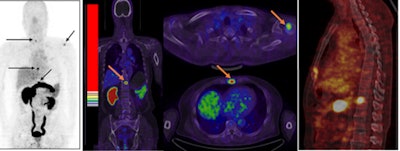

The study included four patients who were newly diagnosed with prostate cancer, nine patients who had received therapy, and five healthy volunteers. Ga-68 BBN-RGD PET/CT detected 20 bone lesions in seven patients either with primary prostate cancer or after radical prostatectomy.

Ga-68 BBN-RGD PET/CT of a 64-year-old man with newly diagnosed prostate cancer shows multiple bone metastases (arrow). Image courtesy of JNM and Jingjing Zhang, Peking Union Medical College in Beijing.The results are better than scanning with a methylene diphosphonate (MDP) radiopharmaceutical, and no adverse side effects were found during the procedure and a two-week follow-up.